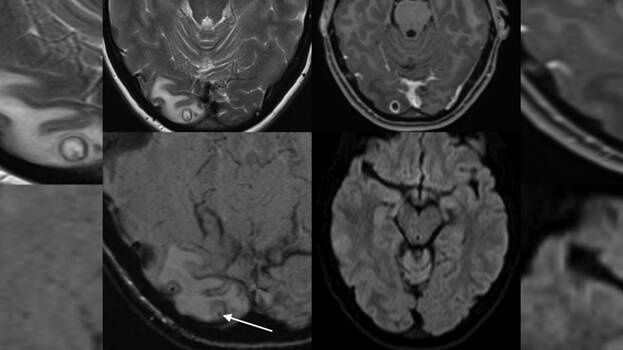

അടുത്തിടെ കഠിനമായ തലവേദന ഒരാഴ്ചയിലേറെ നീണ്ടു നിന്നു. ഒപ്പം കാഴ്ച മങ്ങുകയും ചെയ്തു. ഉടന് തന്നെ യുവതിയെ ആശുപത്രിയില് പ്രവേശിപ്പിച്ചു. ഡോക്ടര്മാര് യുവതിയെ എം.ആര്.ഐ സ്കാന് വിധേയമാക്കി. തലച്ചോറിലെ ട്യൂമറാണെന്ന നിഗമനത്തിലാണ് ഡോക്ടർമാർ എത്തിയത്.. തലയിലെ മുഴ നീക്കം ചെയ്യാനായി ഡോക്ടര്മാര് ശസ്ത്രക്രിയ ആരംഭിച്ചു. എന്നാല് മുഴയ്ക്കുള്ളില് ഡോക്ടര്മാര് കണ്ടത് ഞെട്ടിക്കുന്ന കാഴ്ചയായിരുന്നു.

ടേപ്പ് വേം (Tapeworm ) അഥവാ നാടവിരകളുടെ ലാര്വകളായിരുന്നു അതിനുള്ളില്. ഡോക്ടര്മാര് ശസ്ത്രക്രിയ വിജയകരമായി പൂര്ത്തിയാക്കി. യുവതി സുഖം പ്രാപിച്ചു വരുന്നു. ന്യൂറോസിസ്റ്റിസര്കോസിസ് (Neurocysticercosis ) എന്നാണ് ഈ അവസ്ഥ അറിയപ്പെടുന്നത്. ടേനിയ സോളിയം ( Taenia solium) എന്നറിയപ്പെടുന്ന നാടവിരകളോ അവയുടെ മുട്ടയോ ശരീരത്തിലെത്തുന്നത് വഴിയാണ് ഇവ ഉണ്ടാകുന്നത്.